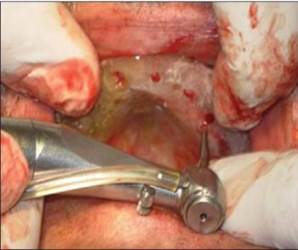

Se planificó un protocolo quirúrgico de dos etapas y se le pidió al paciente que tomara antibióticos y analgésicos antes de la cirugía. El colgajo mucoperióstico se elevó por todo el maxilar superior y la plantilla se colocó en la cresta de la cresta con broca piloto se lleva a cabo [Figura 4] y [Figura 5] . Se colocan herramientas paralelas y se verifican las angulaciones del implante. Se utilizaron taladros secuenciales y se colocaron implantes en el sitio de osteotomía y se introdujeron en el sitio hasta que se enterraron todos los hilos. Se colocaron tornillos de cubierta y se realizó la sutura [Figura 6]. La atención postoperatoria se ha administrado con antibióticos, analgésicos y enjuagues bucales. Se sugirió mantener la higiene bucal y la compresa de hielo si fuera necesario. Se siguió un procedimiento similar para la mandíbula y se realizó la sutura [Figura 7] . Después de 3 meses, el paciente fue retirado del mercado y se realizó una OPG postoperatoria y se verificó su adecuada osteointegración. Después de confirmar la osteointegración, el colgajo se elevó y se retiraron los tornillos de cobertura y se colocó por extensión de la mucosa y esperó durante una semana para que se produzca la curación (Adell R, etal., 1981) [Figura 8] .

Figura 4: Solapa elevadora en el maxilar |

Figura 5: Taladro inicial en posición |